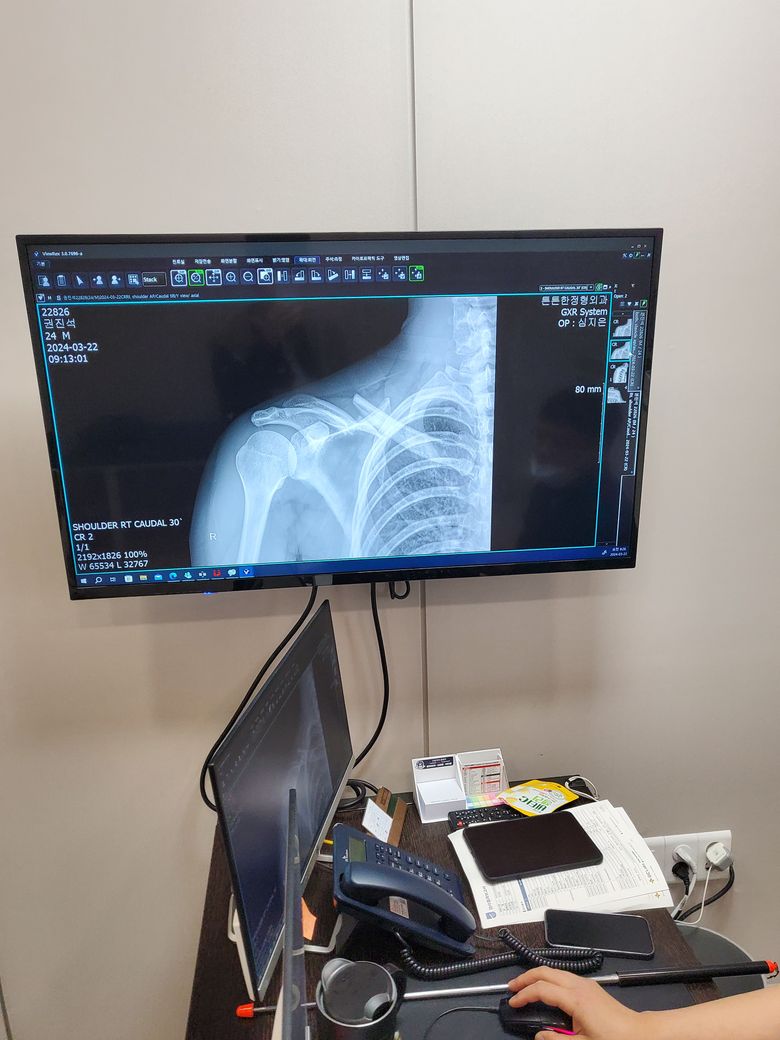

뛰다가 넘어져 다쳤습니다 한번 봐주실수있나요

혹시 상황이 많이안좋은지 수술까지해야하는지 궁금합니다 이게 수술안하고도 나을수 있을까요 지금은 움직이지만 않으면 아프지않은데 아직까지도 안믿겨지네요 ㅠ 답변주시는분 감사합니다

쇄골이 완전히 어긋나버릴 정도의 골절입니다. 수술이 필요할 것이라 보입니다. 치료 잘 받으시기 바랍니다.

쇄골뼈골절입니다.

수술이 필요한경우가있습니다.

진료받은곳에서 수술을 하자하시면 고정하시는것을 추천드립니다.

• 올리신 사진 정보만 보고 정확하게 판단하기는 어렵습니다만, 골절의 정도가 심해 보이고 뼈가 많이 어긋나 쇄골 수술을 받아야 할 가능성이 높아 보이는 소견입니다.